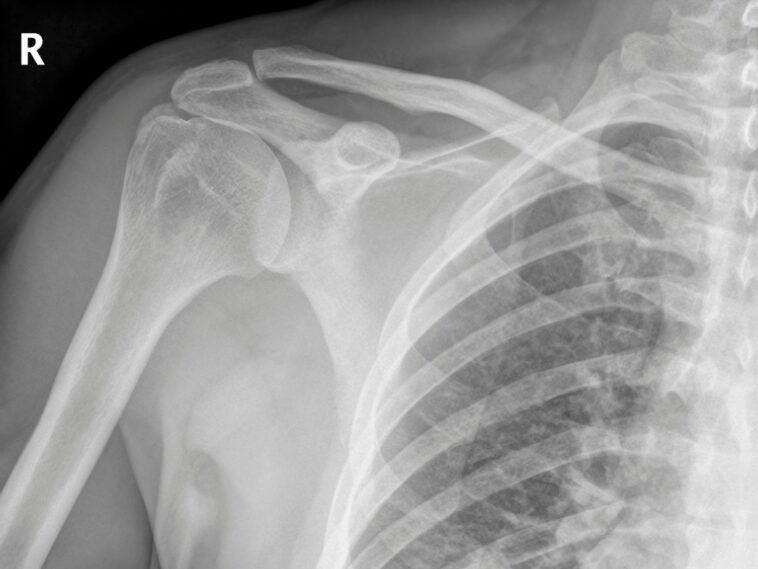

Une nouvelle étude menée par des scientifiques orthopédistes et des ingénieurs biomédicaux de l’Université de Columbia suggère qu’une méthode courante utilisée par les chirurgiens de l’épaule pourrait entraver le succès de la chirurgie de la coiffe des rotateurs.

Au cours de l’opération, les chirurgiens retirent souvent un tissu appelé bourse pour réparer les tendons déchirés de l’articulation de l’épaule, mais l’étude suggère que le petit tissu joue un rôle dans la guérison de l’épaule.

La plupart des lésions des tendons de la coiffe des rotateurs sont dues à l'usure qui s'accumule au fil des années de mouvements répétitifs. Parmi les personnes de plus de 65 ans, environ la moitié ont subi une déchirure de la coiffe des rotateurs, ce qui peut rendre des tâches quotidiennes simples comme se coiffer difficiles et douloureuses.

Plus de 500 000 interventions chirurgicales de la coiffe des rotateurs sont pratiquées chaque année aux États-Unis pour réparer ces blessures, restaurer l’amplitude des mouvements et soulager la douleur, mais elles échouent fréquemment, allant d’une intervention sur cinq chez les jeunes patients à 94 % chez les patients âgés présentant de grandes déchirures.

Les réparations de la coiffe des rotateurs échouent généralement en raison d’une mauvaise cicatrisation entre le tendon et l’os à l’endroit où le tendon est rattaché à l’os.